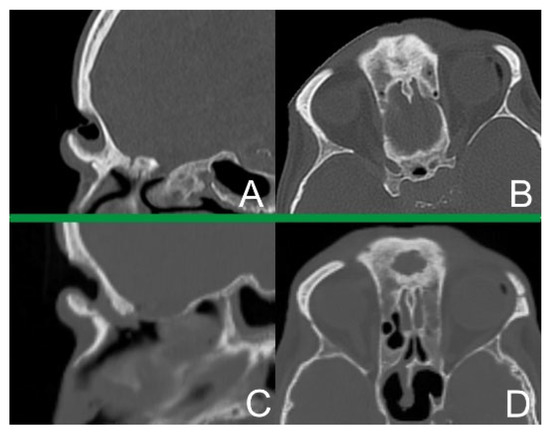

The patient underwent a non-contrast CT scan (Revolution Evo system, 64 rows, GEHealthcare). The obtained image revealed a defect of bone and soft tissue in the glabella area, about 3 cm in diameter, and an overgrowth of bone tissue across the entire width of the nasofrontal duct. (Figure 3A,B)

Figure 3. (A) Condition after the first CT scan-sagittal plane. (B) Condition after the first CT scan-transverse plane. (C) CT scan 14 days after first procedure-sagittal plane. (D) CT scan 14 days after first procedure-transverse plane.

Fourteen days following the laryngological procedure, the created canal was found to be overgrown and the nasofrontal duct lacked patency. A repeat CT scan of the facial part of the cranium confirmed that the canal was overgrown with soft tissue compared with the previous examination (Figure 3C,D).